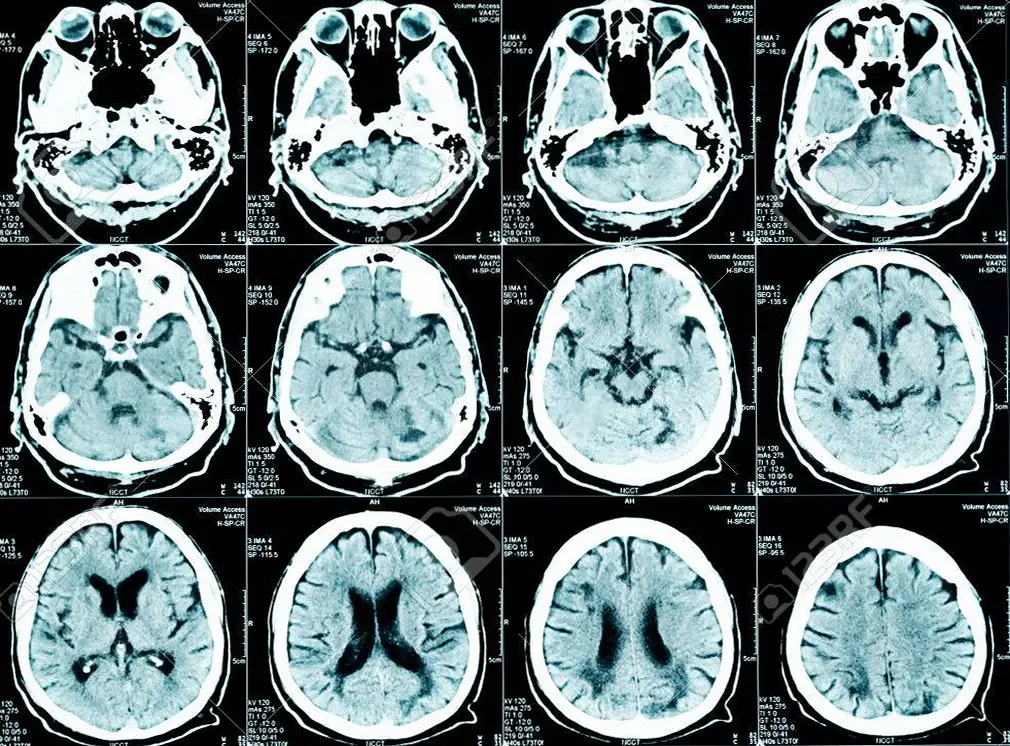

Megaloencefalia: cause, sintomi, diagnosi, terapia e prognosi

MEDICINA ONLINE NEUROLOGIA NEUROLOGO CERVELLO ENCEFALO SISTEMA NERVOSO RISONANZA MAGNETICA RM TAC TC TOMOGRAFIA COMPUTERIZZATA DIAGNOSTICA PER IMMAGINI RADIOGRAFIA RXLa megaloencefalia o megalencefalia (dal greco antico μέγας megas, “grande” e ἐγκέφαλος enképhalos, “cervello”) è un’anomalia molto rara, spesso congenita, che consiste in un cervello e un cranio insolitamente grandi (macrocefalia), in assenza di Continua a leggere

Emimegaloencefalia: cause, sintomi, diagnosi, terapia e prognosi

MEDICINA ONLINE NEUROLOGIA NEUROLOGO CERVELLO ENCEFALO SISTEMA NERVOSO RISONANZA MAGNETICA RM TAC TC TOMOGRAFIA COMPUTERIZZATA DIAGNOSTICA PER IMMAGINI RADIOGRAFIA RXL’emimegaloencefalia (anche chiamata “emimegalencefalia” o “megaloencefalia unilaterale“) è una condizione congenita rara che consiste in una crescita eccessiva di uno dei due emisferi cerebrali o di una parte di esso, mentre le dimensioni dell’altro emisfero rimangono nei Continua a leggere